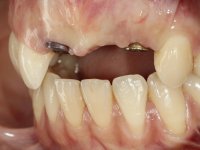

In the initial phase, it was proposed to the patient to perform the surgical implant exposure and after clinical evaluation, make prosthetic decisions. Once the healing screw was placed and the soft tissues were healed, an inadequate position of the implant was found. In view of the dramatic situation, the patient was proposed to remove the implant and put a new one after tissue regeneration. This proposal was rejected by the patient, who suggested temporary rehabilitation of the current implant. A new proposal was then made, to rehabilitate the implant, consisting of a screwed abutment, and on this, the placement of an acrylic crown with coronal and gingival components. After 6 years with the provisional treatment, the patient appeared in consultation with an abscess in tooth 1.1. After clinical and imaging analysis, it was decided to remove teeth 1.1 and 2.2, submerge the implant, place two implants at the site of 1.1 and 2.2 and perform adequate tissue regeneration. Temporization would be done with a provisional 3-element bridge, adhered with a net to the neighboring teeth. After osseointegration, definitive rehabilitation would be done with a 3-element bridge, including zirconia infrastructure and ceramic cover.

The surgical implant exposure and the healing screw placement proved to be a negative surprise regarding its position. Since the proposed removal of the implant was refused, we advanced to its provisional rehabilitation. An open tray impression technique was done, and a screwed abutment with a coronal and gingival component and an acrylic crown were made in the laboratory, using these two components. The provisional crown was placed in the mouth until a final decision was made. Six years passed before the patient returned to the clinic with an abscess on tooth 1.1. The choice to remove teeth 1.1 and 2.2 was made, to create a provisional 3-element bridge with a net to be adhered to the adjacent teeth. Surgery was planned and performed, placing the two implants at the site of 1.1 and 2.2, and the implant at the 2.1 site was cut with the objective of submerging it, while adequate tissue regeneration was performed (Surgical Work performed By Dr. Manuel Neves). During osseointegration, the patient used the fixed provisional bridge. A first impression was made for confection of a zirconia screwed provisional bridge, which worked the soft tissues for twelve weeks. The definitive impression was made with the individualisation of custom impression copings. Final rehabilitation was done with ceramized abutments, and also a bridge with zirconia infrastructure and ceramic cover. Due to the inclination of the implant placed at the site of tooth 1.1, the bridge required cemented fixation.